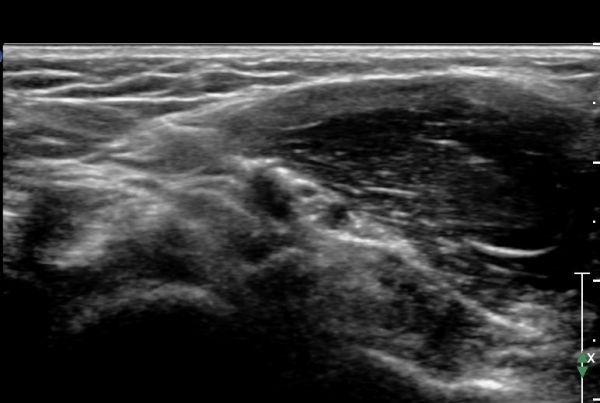

ÃÊÀ½ÆÄ °Ë»ç : ȸ³»±Ù ±ÙÀ§ºÎ¿¡¼ Á¤Á߽Űæ Ⱦ´Ü¸é°Å»ç¿¡¼ ƯÀÌ ¼Ò°ßÀ» º¸ÀÌÁö ¾ÊÀ¸³ª(»çÁø 1) ȸ³»±Ù ¿ä°ñµÎ ±â½ÃºÎ ¿¡¼ Á¤Á߽ŰæÀÇ ±¹°íÀû ¾Ð¹Ú ¹× ÆíÆòȰ¡ °üÂûµÊ(»çÁø 2). ÀÌ·± º¯È´Â °ÇÃø(»çÁø 5)°ú ºñ±³ÇÏ¸é ¶Ñ·ÇÇÔ.